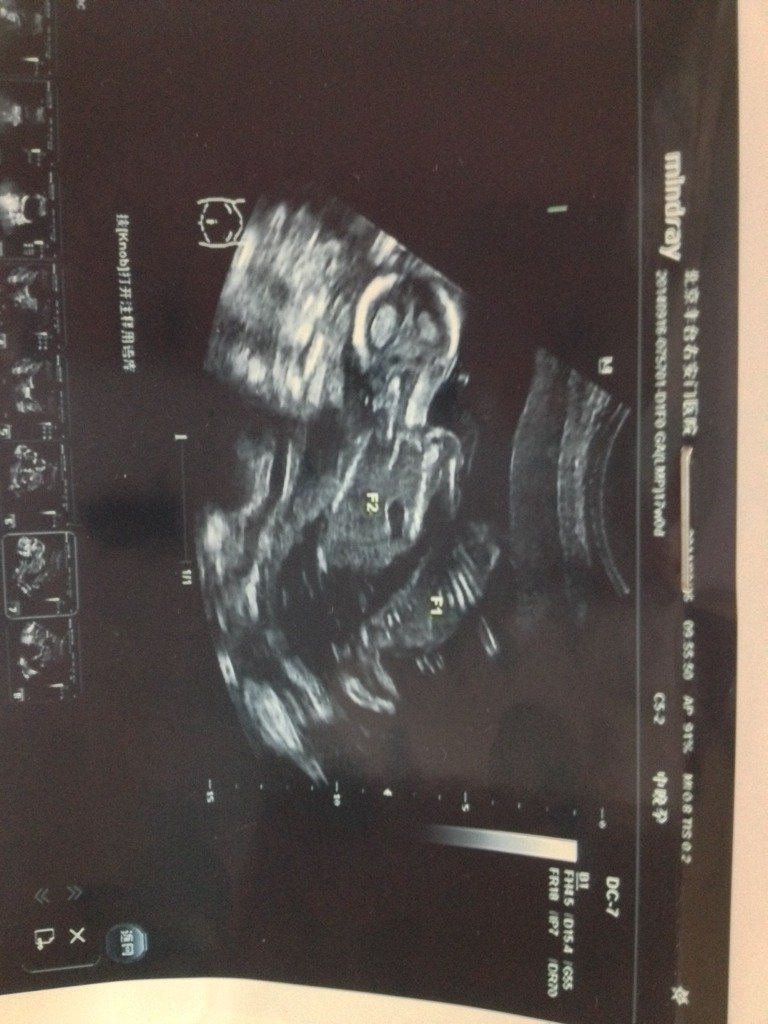

医生说我双胎共用一个胎盘麻烦医生帮忙看看 医生说我双胎共用一个胎盘麻烦医生帮忙看看.. 点击展开 __文呓青年 , 2014-09-16 15:23 为您推荐: 其他回答 双胎共用一个胎盘也是一种正常的情况,你的属于单卵双胎,还有一种情况是双卵双胎。 金牛李世峰 2014-09-16 15:25 相关问题 有医生在吗?怀双胞胎,共用一个胎盘,是不是性别也一样? 麻烦医生帮忙看看我的胎心监护结果,今天去医院吸了氧再做得胎心监护,医生说没有什么反应,情况不好,但 医生说羊水不多不少,胎盘很好 说胎心很好,预产期跟宝宝知道这个软件里面算得一样